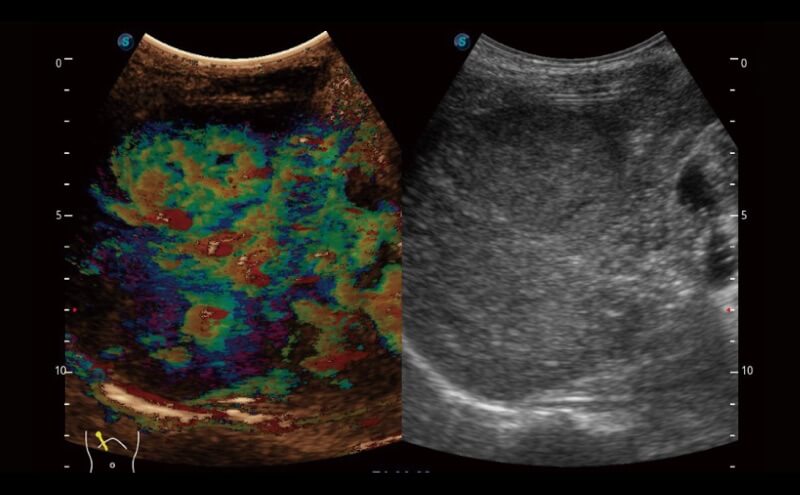

Die Bildqualität liegt immer im Zentrum definierter klinischer Ergebnisse. ELITE liefert eine leistungsstarke und klare Bildgebung, die durch eine leistungsstarke Architektur, hochmoderne Sonden und ausgeklügelte Verarbeitungsalgorithmen erzeugt wird, für ein höheres Maß an Klarheit und Vertrauen.

Die Anpassung der Bildparameter erfolgt nun nicht mehr mühsam. Auto B/C hilft dabei, die Bildqualität unter B- und Farbdoppler-Modus mit nur einem Klick zu optimieren. Mehrere Parameter wie Gain, TGC, ROI-Position, Lenkwinkel usw. sind in dieser vollautomatisierten Methode enthalten.